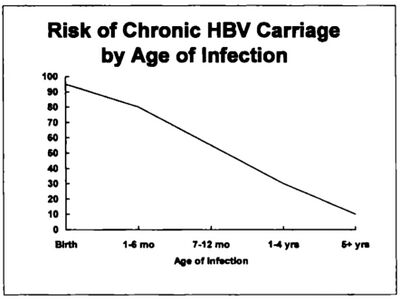

تتطور 10٪ تقريباً من كل الإنتانات الحادة بڤيروس HBV إلى إنتان مزمن، ويتناقص خطر الإنتان المزمن بڤيروس HBV مع التقدم بالعمر. إن ما يزيد عن 90% من الرضع الذين يكتسبون إنتان HBV من أمهاتهم عند الولادة يصبحون حملة مزمنين. في حين تكون هذه النسبة 30 % - 50 ٪ عند الأطفال بين عمر 1- 5 سنوات. أما خطر الإنتان المزمن عند البالغين فهو 6 - 10 ٪.

وتوجد عدوى ڤيروس التهاب الكبد ب المزمنة في 0.5٪ من البالغين في أمريكا الشمالية، وفي 0.1٪ إلى 20٪ في أجزاء أخرى من العالم. وبعد العدوى الحادة بڤيروس التهاب الكبدي ب، يختلف خطر تطور العدوى إلي مزمنة عكسياً مع السن؛ وتحدث العدوى المزمنة بڤيروس الالتهاب الكبدي ب في حوالي 90٪ من الرضع الذين يصابون بالعدوى عند الولادة، و20٪-50٪ من الأطفال الذين يصابون بالعدوى بين سن 1-5 سنوات، و1٪-10٪ في الأشخاص المصابين بالعدوى كأطفال أكبر من ذلك والبالغين. وعدوى ڤيروس الالتهاب الكبدي ب المزمنة شائعة في الأشخاص الذين لديهم عوز مناعي. وقد يكون أو لا يكون لدى المصابين بالعدوى المزمنة سوابق التهاب كبد سريري. ويشاهد في حوالي الثلث ارتفاع في ناقلات الأمين؛ وتتراوح نتائج الخزعة من "خزعة سوية" إلى التهاب كبدي نخري وخيم مع أو دون تشمع. ويقدر أن 15٪-25٪ من الأشخاص المصابين بعدوى ڤيروس التهاب الكبد (ب) المزمن سوف يموتون موتاً مبكراً إما بسبب التشمع أو بسبب السرطانة الخلوية الكبدية. وڤيروس التهاب الكبد ب هو السبب في حوالي 80٪ من مجموع حالات السرطانة الخلوية الكبدية على نطاق العالم.

يقوم الأطفال بإزالة العدوى أقل بكثير من الكبار. وينتقل أكثر من 95 ٪ من الاشخاص الذين يصابون بالعدوى مثل البالغين أو الأطفال الأكبر سنا إلى مرحلة الشفاء الكامل وتطوير مناعة وقائية لهذا الڤيروس. ومع ذلك، تنخفض هذه النسبة إلى 30 ٪ للأطفال الأصغر سنا، ويكون 5 ٪ فقط من المواليد الجدد الذين يكتسبون العدوى من أمهاتهم عند الولادة قادرين على إزالة العدوى [26]. هذه الفئة لديها 40 ٪ خطر الموت خلال الحياة من تليف الكبد أو سرطان الكبد.[27] ومن بين هؤلاء المصابين الذين تتراوح أعمارهم من شهر إلى ستة، 70 ٪ قادر على التخلص من العدوى.[28]